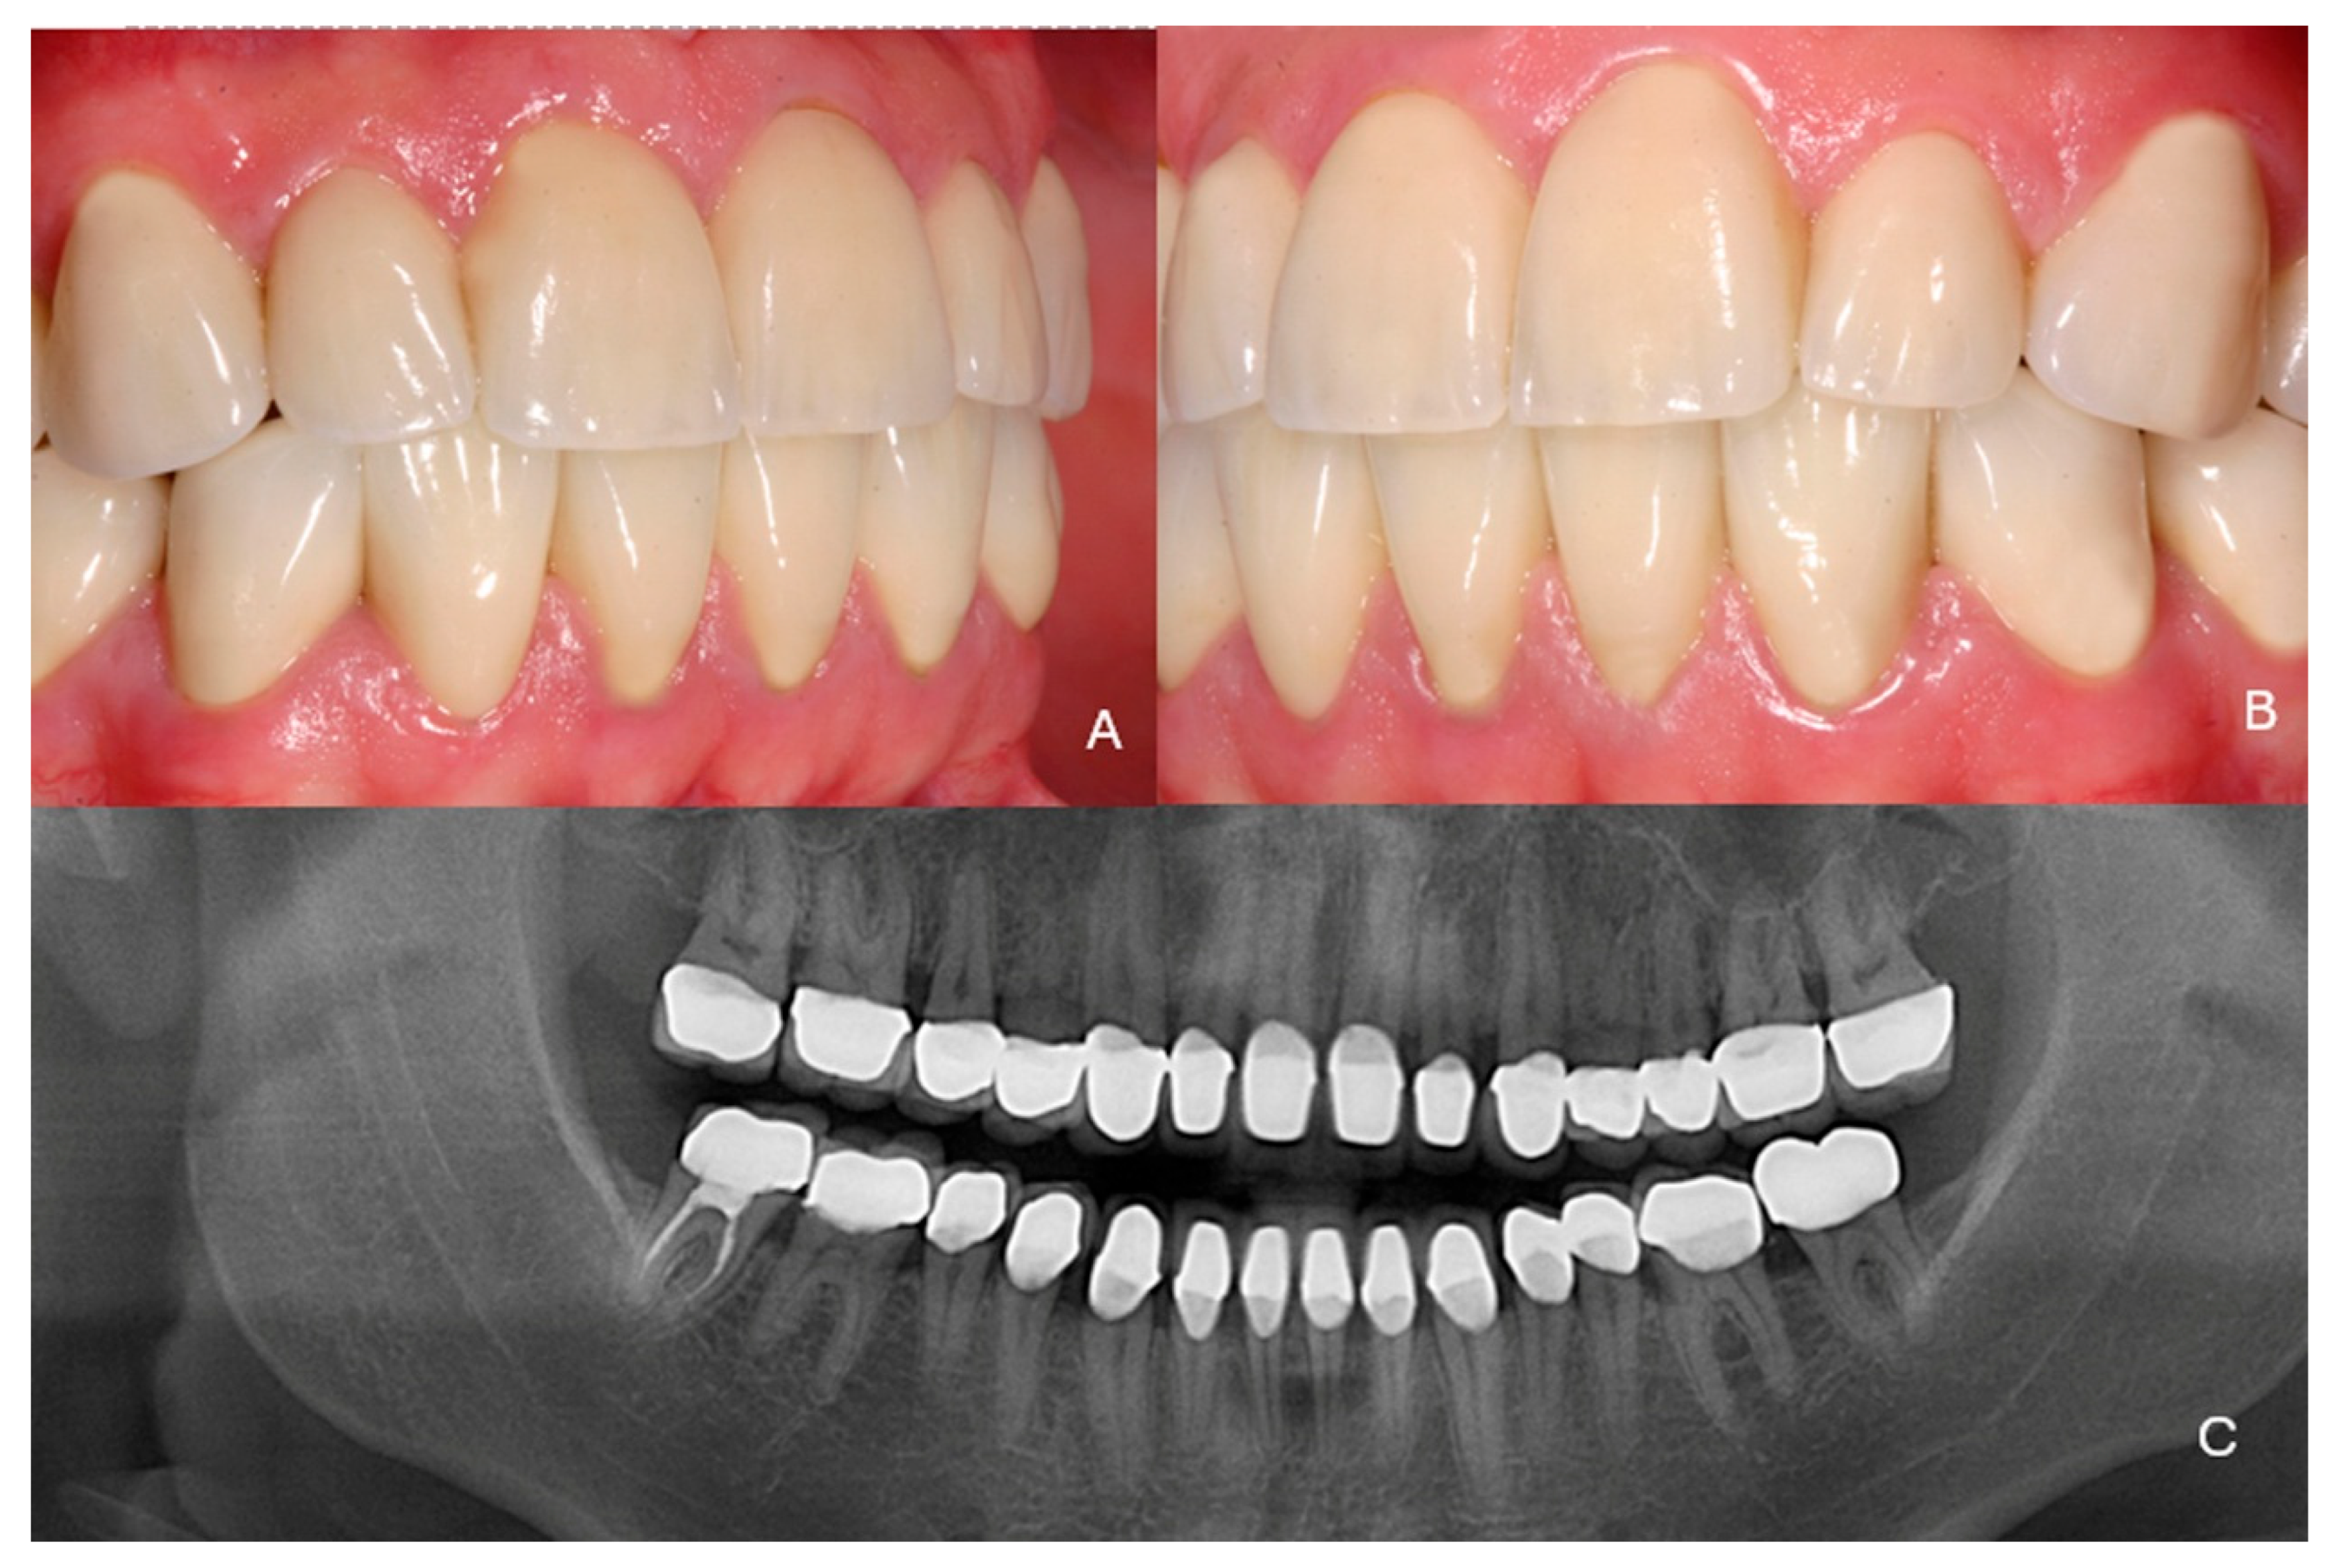

2. Case Presentation